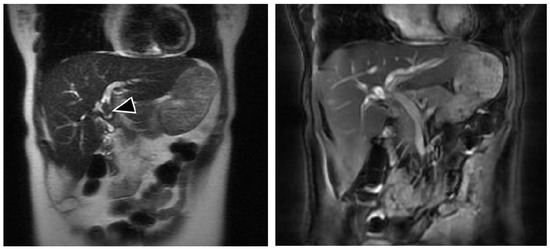

Transjejunal Laparoscopic Assisted ERCP in a Patient with Roux-en-Y Hepaticojejunostomy

2. Case Presentation